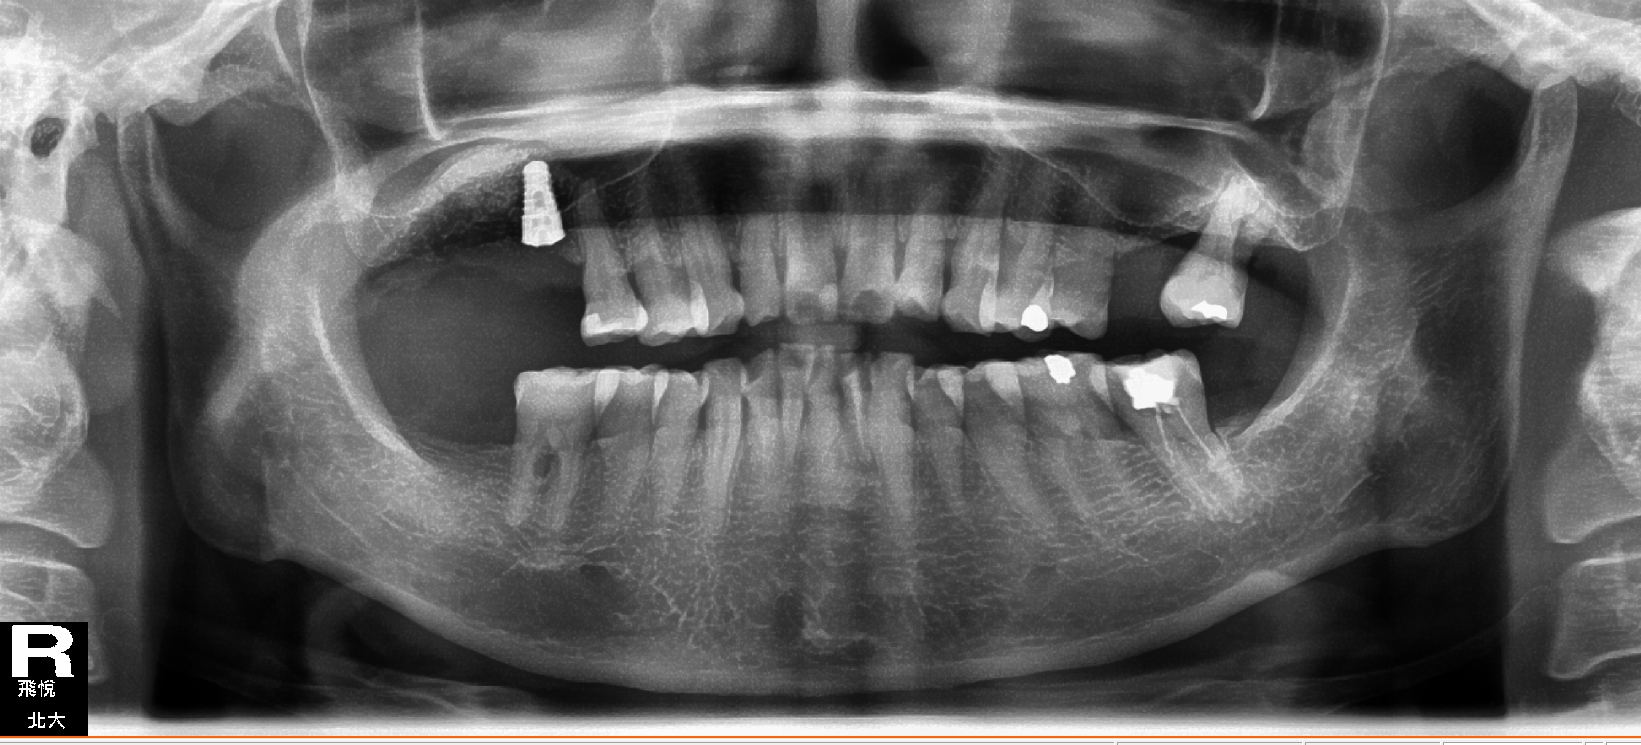

飛悅.北大牙醫聯合診所「從齒,我們想得比您更遠」 Beyond Dental Clinic 植牙+鼻竇增高手術**一次完成 首頁 診療項目 人工植牙 植牙+鼻竇增高手術**一次完成 案例分享 植牙+鼻竇增高手術~一次完成 看看我們的蘇醫師多麼專注的樣子~~ 其實手術沒有大家想像中的困難 今日手術時間才1小時喔! ×

植牙+鼻竇增高手術**一次完成 首頁 診療項目 人工植牙 植牙+鼻竇增高手術**一次完成 案例分享 植牙+鼻竇增高手術~一次完成 看看我們的蘇醫師多麼專注的樣子~~ 其實手術沒有大家想像中的困難 今日手術時間才1小時喔!